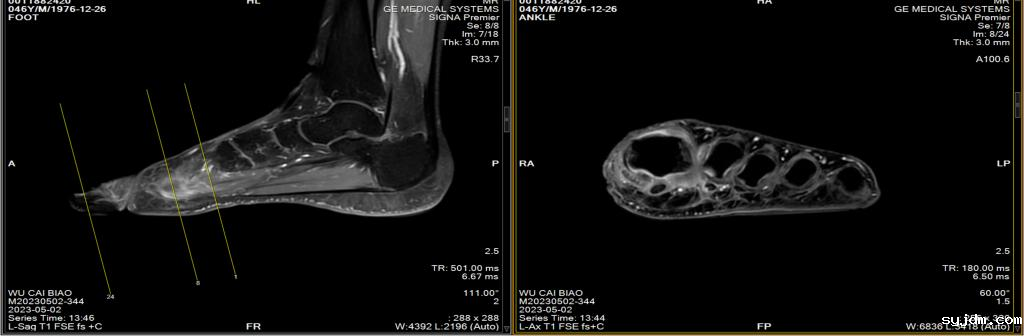

磁共振左足平扫增强

左足第一跖骨、第一足母趾近节趾骨、第一趾远节趾骨及第三趾中节趾骨多发异常信号灶,周围软组织肿胀,性质待定:炎症?请结合临床。

图B:患者趾骨水肿

MRI(金标准):T2加权像高信号(骨髓水肿),增强后强化,可发现早期无症状病灶。